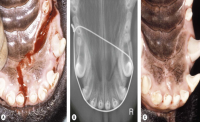

Symphyseal Separation and Fractures Involving the Incisive Region

Oral and Maxillofacial Surgery in Dogs and Cats, 2012, Pages 265-274. Authors: Ulrike Matis, Roberto Köstlin

Separation of the mandibular symphysis

Cerclage wiring

Transfixation pin

Palatine fractures

Plate fixation

Intraoral acrylic or composite splints

Alveolar process fractures and (sub)luxation of mandibular and maxillary incisor teeth

Alveolar process fractures and (sub)luxation of mandibular and maxillary canine teeth

Labial reverse suture through buttons